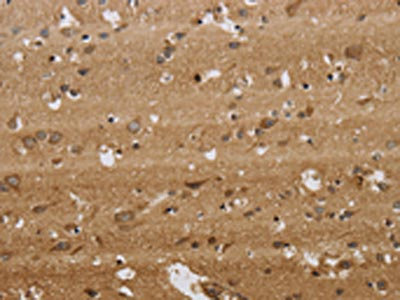

The image on the left is immunohistochemistry of paraffin-embedded Human brain tissue using CSB-PA252563(KCNMB2 Antibody) at dilution 1/40, on the right is treated with synthetic peptide. (Original magnification: ×200)